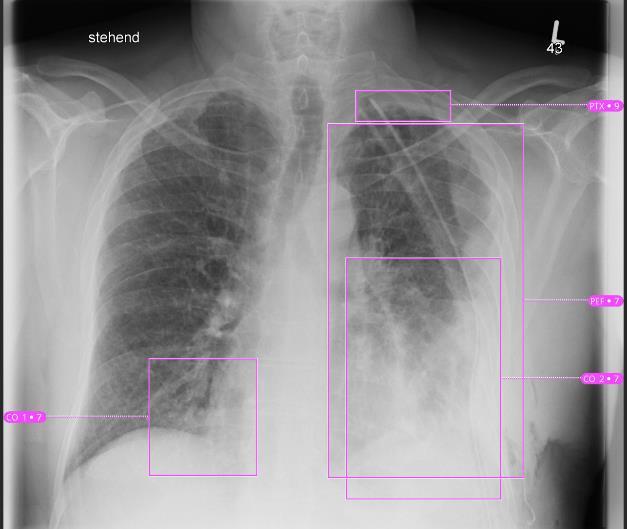

Lung cancer screening Chest CT Pulmonary lesions – Chest X-Ray

Supports 200+ organs at risk + clinical target volumes. 1000+ sites, 1.2M cancer patients / year

• Includes lymph node stations in Pelvic, Head & Neck, and Breast Cancer

• 82% time savings